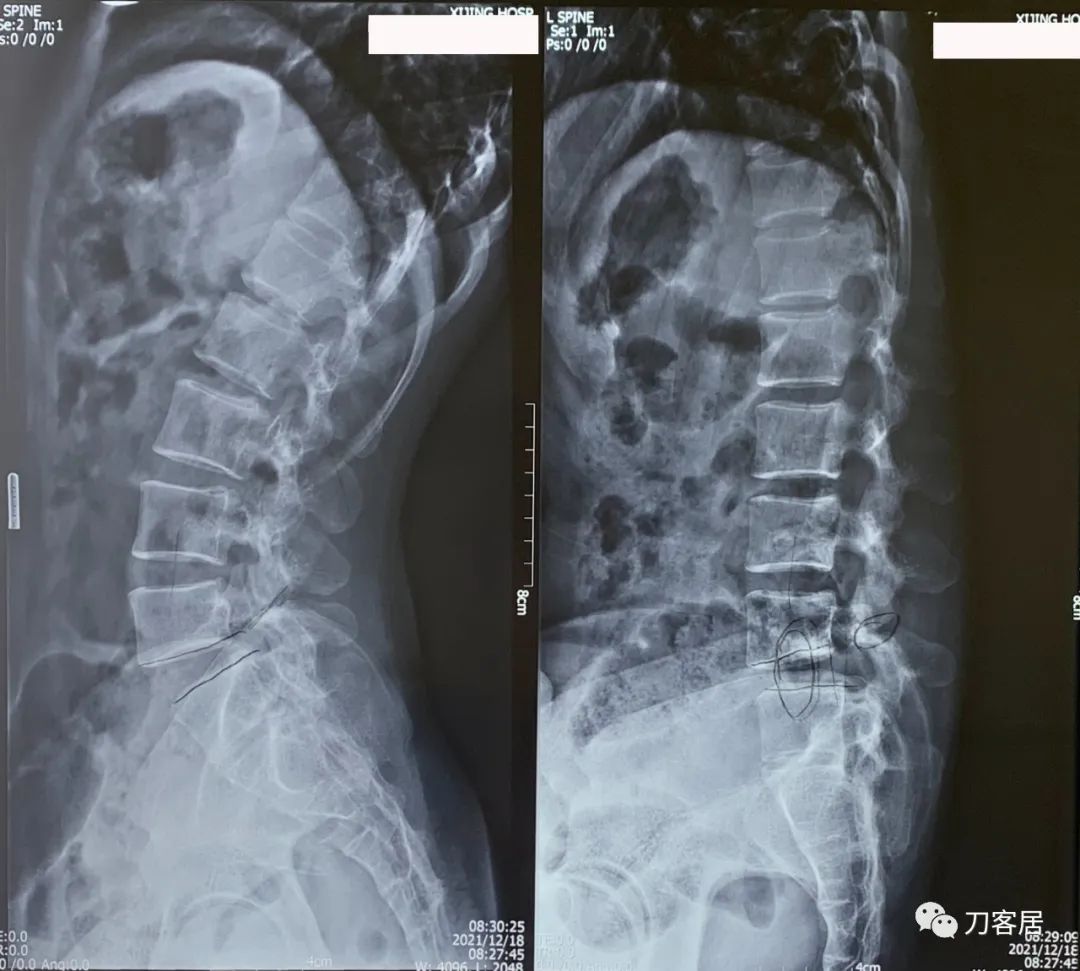

腰椎X线片提示腰5峡部裂,1度前滑脱。

图6. 20211218西京医院腰椎过伸过屈侧位X线片